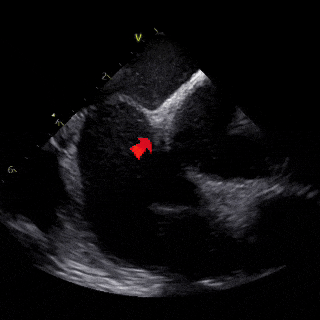

ICE下可见封堵器成型良好,左右盘面牢牢夹持房间隔,且无残余分流,封堵手术成功

各房、室内径正常,主动脉窦部内径正常,升主动脉内径稍增宽。各瓣膜形态、回声及开放活动未见异常。左室壁厚度正常,静息状态下左室壁收缩运动未见明显异常。房间隔中部可见封堵器强回声,位置固定。室间隔回声未见中断。心包及心包腔未见异常。

CDFI:房间隔处未见房水平分流,二、三尖瓣房侧及主动脉瓣下可见少许反流束,测TV反流速度2.3m/s。二尖瓣口舒张期血流速度:E/A>1。组织多普勒显像(TDI):二尖瓣环E′/A′<1。

超声诊断:

卵圆孔未闭封堵术后:升主动脉稍增宽、主动脉瓣反流(轻度)、二尖瓣反流(轻度)、三尖瓣反流(轻度)、左室松弛性异常、左室收缩功能正常。